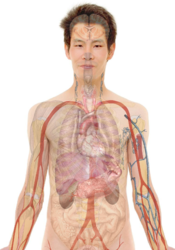

File:Tuberculosis symptoms.svg

| DescriptionTuberculosis symptoms.svg |

English: Main symptoms of different variants and stages of tuberculosis (See Wikipedia:Tuberculosis), with many symptoms overlapping with other variants, while others are more (but not entirely) specific for certain variants. Multiple variants may be present simultaneously.

Pulmonary tuberculosis symptoms

Extrapulmonary tuberculosis symptoms